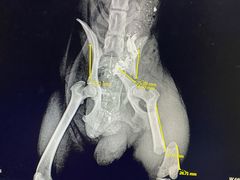

• 思宇宠物医院

• -思宇宠物医院

麦兜小子 | 20-04-14